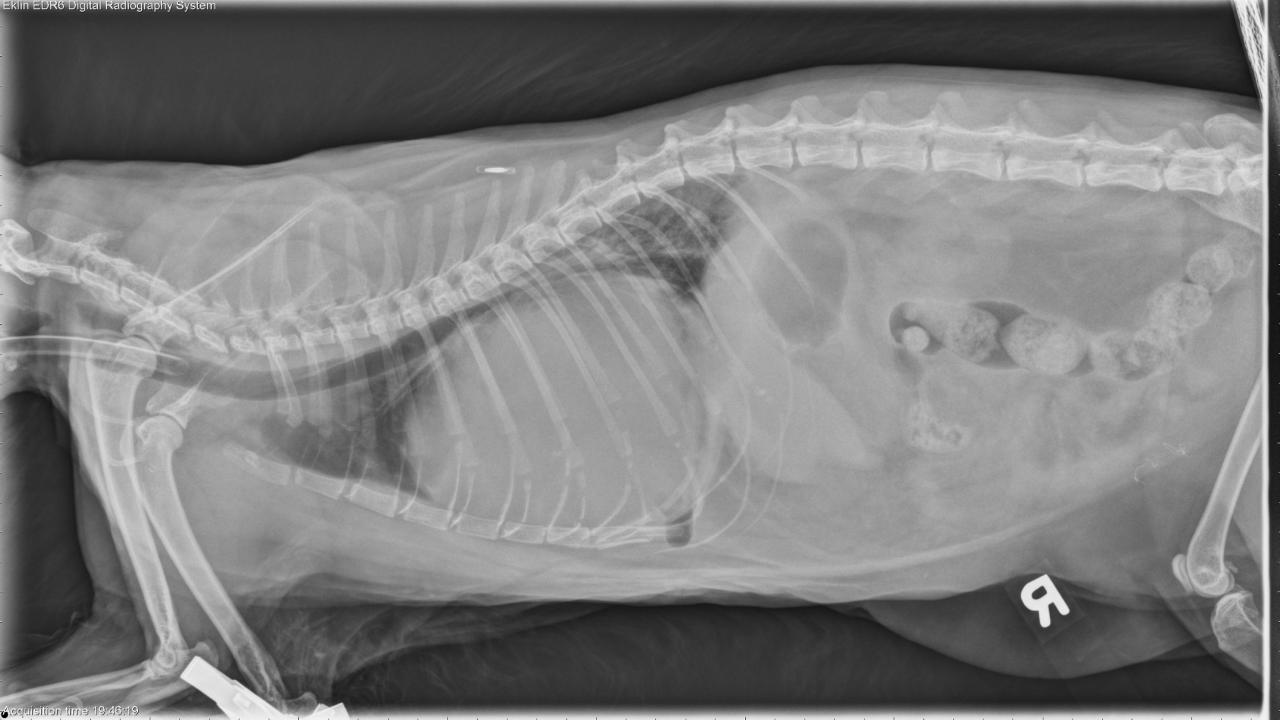

Historical diaphragmatic hernia, incidental diagnosis three years ago. The patient has been intermittently coughing for the past few years. The past month, the coughing is more frequent / severe, with respiratory distress. This past week, the patient has had labored breathing. Respiratory distress at the vet today. The patient was referred and on presentation, was cyanotic and was subsequently intubated.